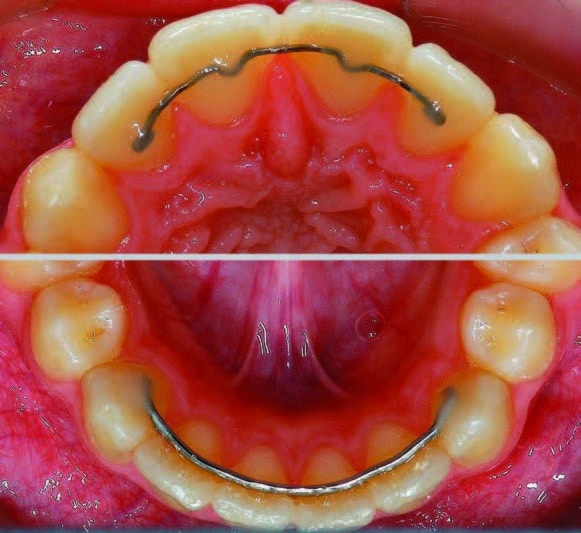

On collait au début le fil de contention aux quatre incisives ; (Fig.6). Aujourd’hui, nous collons presque exclusivement les incisives, ainsi que les deux canines ; (Fig.7), les fameuses « social six ». Initialement, les fils étaient pliés avec un « V » central sur la surface palatine des dents. Ces contentions offrent une plus grande surface de collage.Toutefois, pour réduire au minimum la surface de collage en cas d’un mors profond (deep bite) ; (Fig.8), on renonce à la forme avec le « V » et on plie le fil de manière rectiligne ou avec une légère courbure sur chaque dent ; (Fig.9).